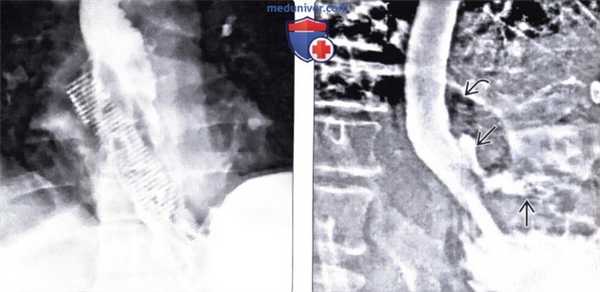

(Слева) На рентгенограмме пищевода визуализируется тень пластиковой расчески в проекции дистальных отделов пищевода и проксимальных отделов желудка. При поверхностном взгляде на рентгенограмму создается впечатление, что имеющиеся на ней изменения обусловлены наличием обходного стента, установленного пациенту с обструктивным поражением пищевода.

(Справа) На рентгенограмме в косой проекции, полученной после эндоскопического извлечения инородного тела (ИТ), определяется утечка контраста и свободный газ в брюшной полости. В этом случае пациенту потребовалось оперативное вмешательство.